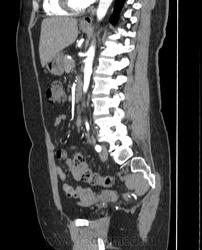

Женщина 50 лет, жалобы на тянущие боли в области малого таза, менопауза 1год, патологических выделений из влагалища не отмечает. На УЗИ киста правого яичника, левый яичник нормальный, объемное образование кишечника(?). На МРТ кистозно-солидное образование левого яичника, кишечника(?). Рекомендуют КТ. Как отдифференцировать? Киста справа понятно, слева то ли в яичнике, то ли... не было бы УЗИ и МРТ подумал бы на лейомиому матки. В понедельник будет делать ирригоскопию.